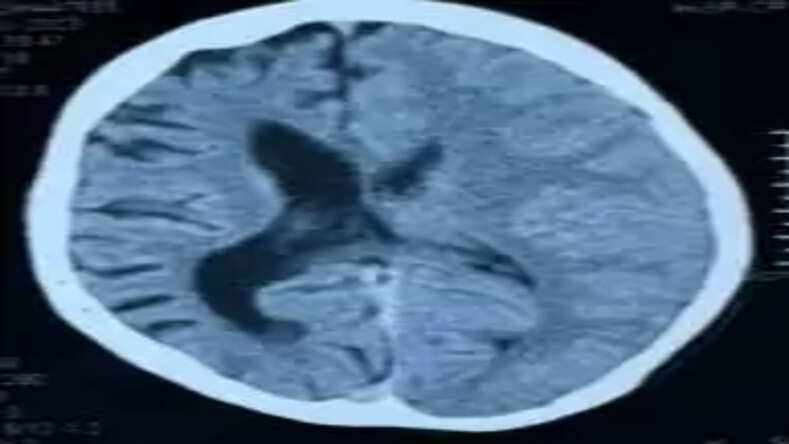

शाहजहाँपुर: शाहजहाँपुर के एक 15 वर्षीय किशोर में 10 वर्षों से बार-बार होने वाले मिर्गी के दौरे (रीकरेंट सीज़र) के कारण गंभीर न्यूरोलॉजिकल बीमारी का पता चला है। इस किशोर को परिजनों द्वारा लंबे समय से दौरे आने, पढ़ाई में कठिनाई और शरीर के एक हिस्से में कमजोरी की शिकायत के साथ न्यूरोलॉजी परामर्श के लिए लाया गया था। विस्तृत जांच और एमआरआई ब्रेन कराने के बाद इस दुर्लभ बीमारी का निदान डाइके–डेविडॉफ–मैसन सिंड्रोम (Dyke Davidoff Masson Syndrome) के रूप में किया गया।

डॉ. मो. इमरान के अनुसार यह एक दुर्लभ न्यूरोलॉजिकल स्थिति है, जिसमें बचपन में किसी कारणवश मस्तिष्क के एक हिस्से का विकास ठीक से नहीं हो पाता या उसमें क्षति हो जाती है। इसके परिणामस्वरूप मरीज में मिर्गी के दौरे, शरीर के एक हिस्से में कमजोरी, बोलने या सीखने में परेशानी देखी जा सकती है।